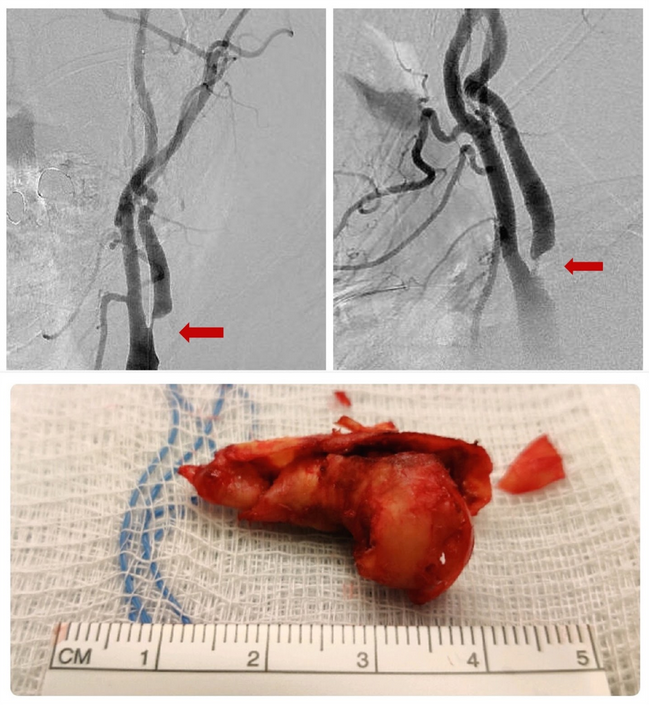

Carotid Endarterectomy: For patients with significant narrowing of the carotid artery that show symptoms of stroke, surgery can be recommended. Carotid endarterectomy surgery involves opening and clamping the artery above and below the plaque buildup and removing it while the artery is clamped.

Figure 3. Carotid Endarterectomy – Cervical angiogram anterior view (upper left) and lateral view (upper right) demonstrating severe carotid stenosis (red arrows). After carotid endarterectomy reopened the vessel, an antherosclerotic plaque that was removed from the diseased vessel wall is pictured (lower image).